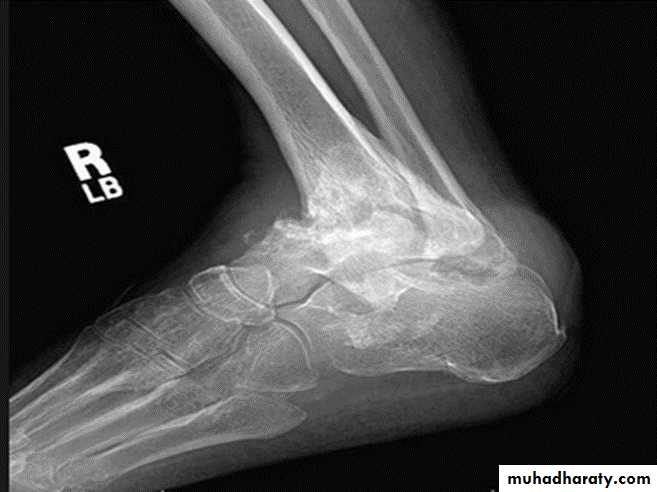

NEUROPATHIC ARTHRITIS (CHARCOT'S JOINT)

Primary loss of sensation in a joint leads to arthropathy. Distribution helps determine etiology.Causes

Diabetes neuropathy: usually foot

Tertiary syphilis : usually knee

Syringomyelia: usually shoulder

Radiographic features:

Common to all types

*Joint instability: subluxation or dislocation

*Prominent joint effusion

--- Hypertrophic type, 20%

Marked fragmentation of articular bone

Much reactive bone

--- Atrophic type, 40°/0

Bone resorption of articular portion

--- Combined type, 40%